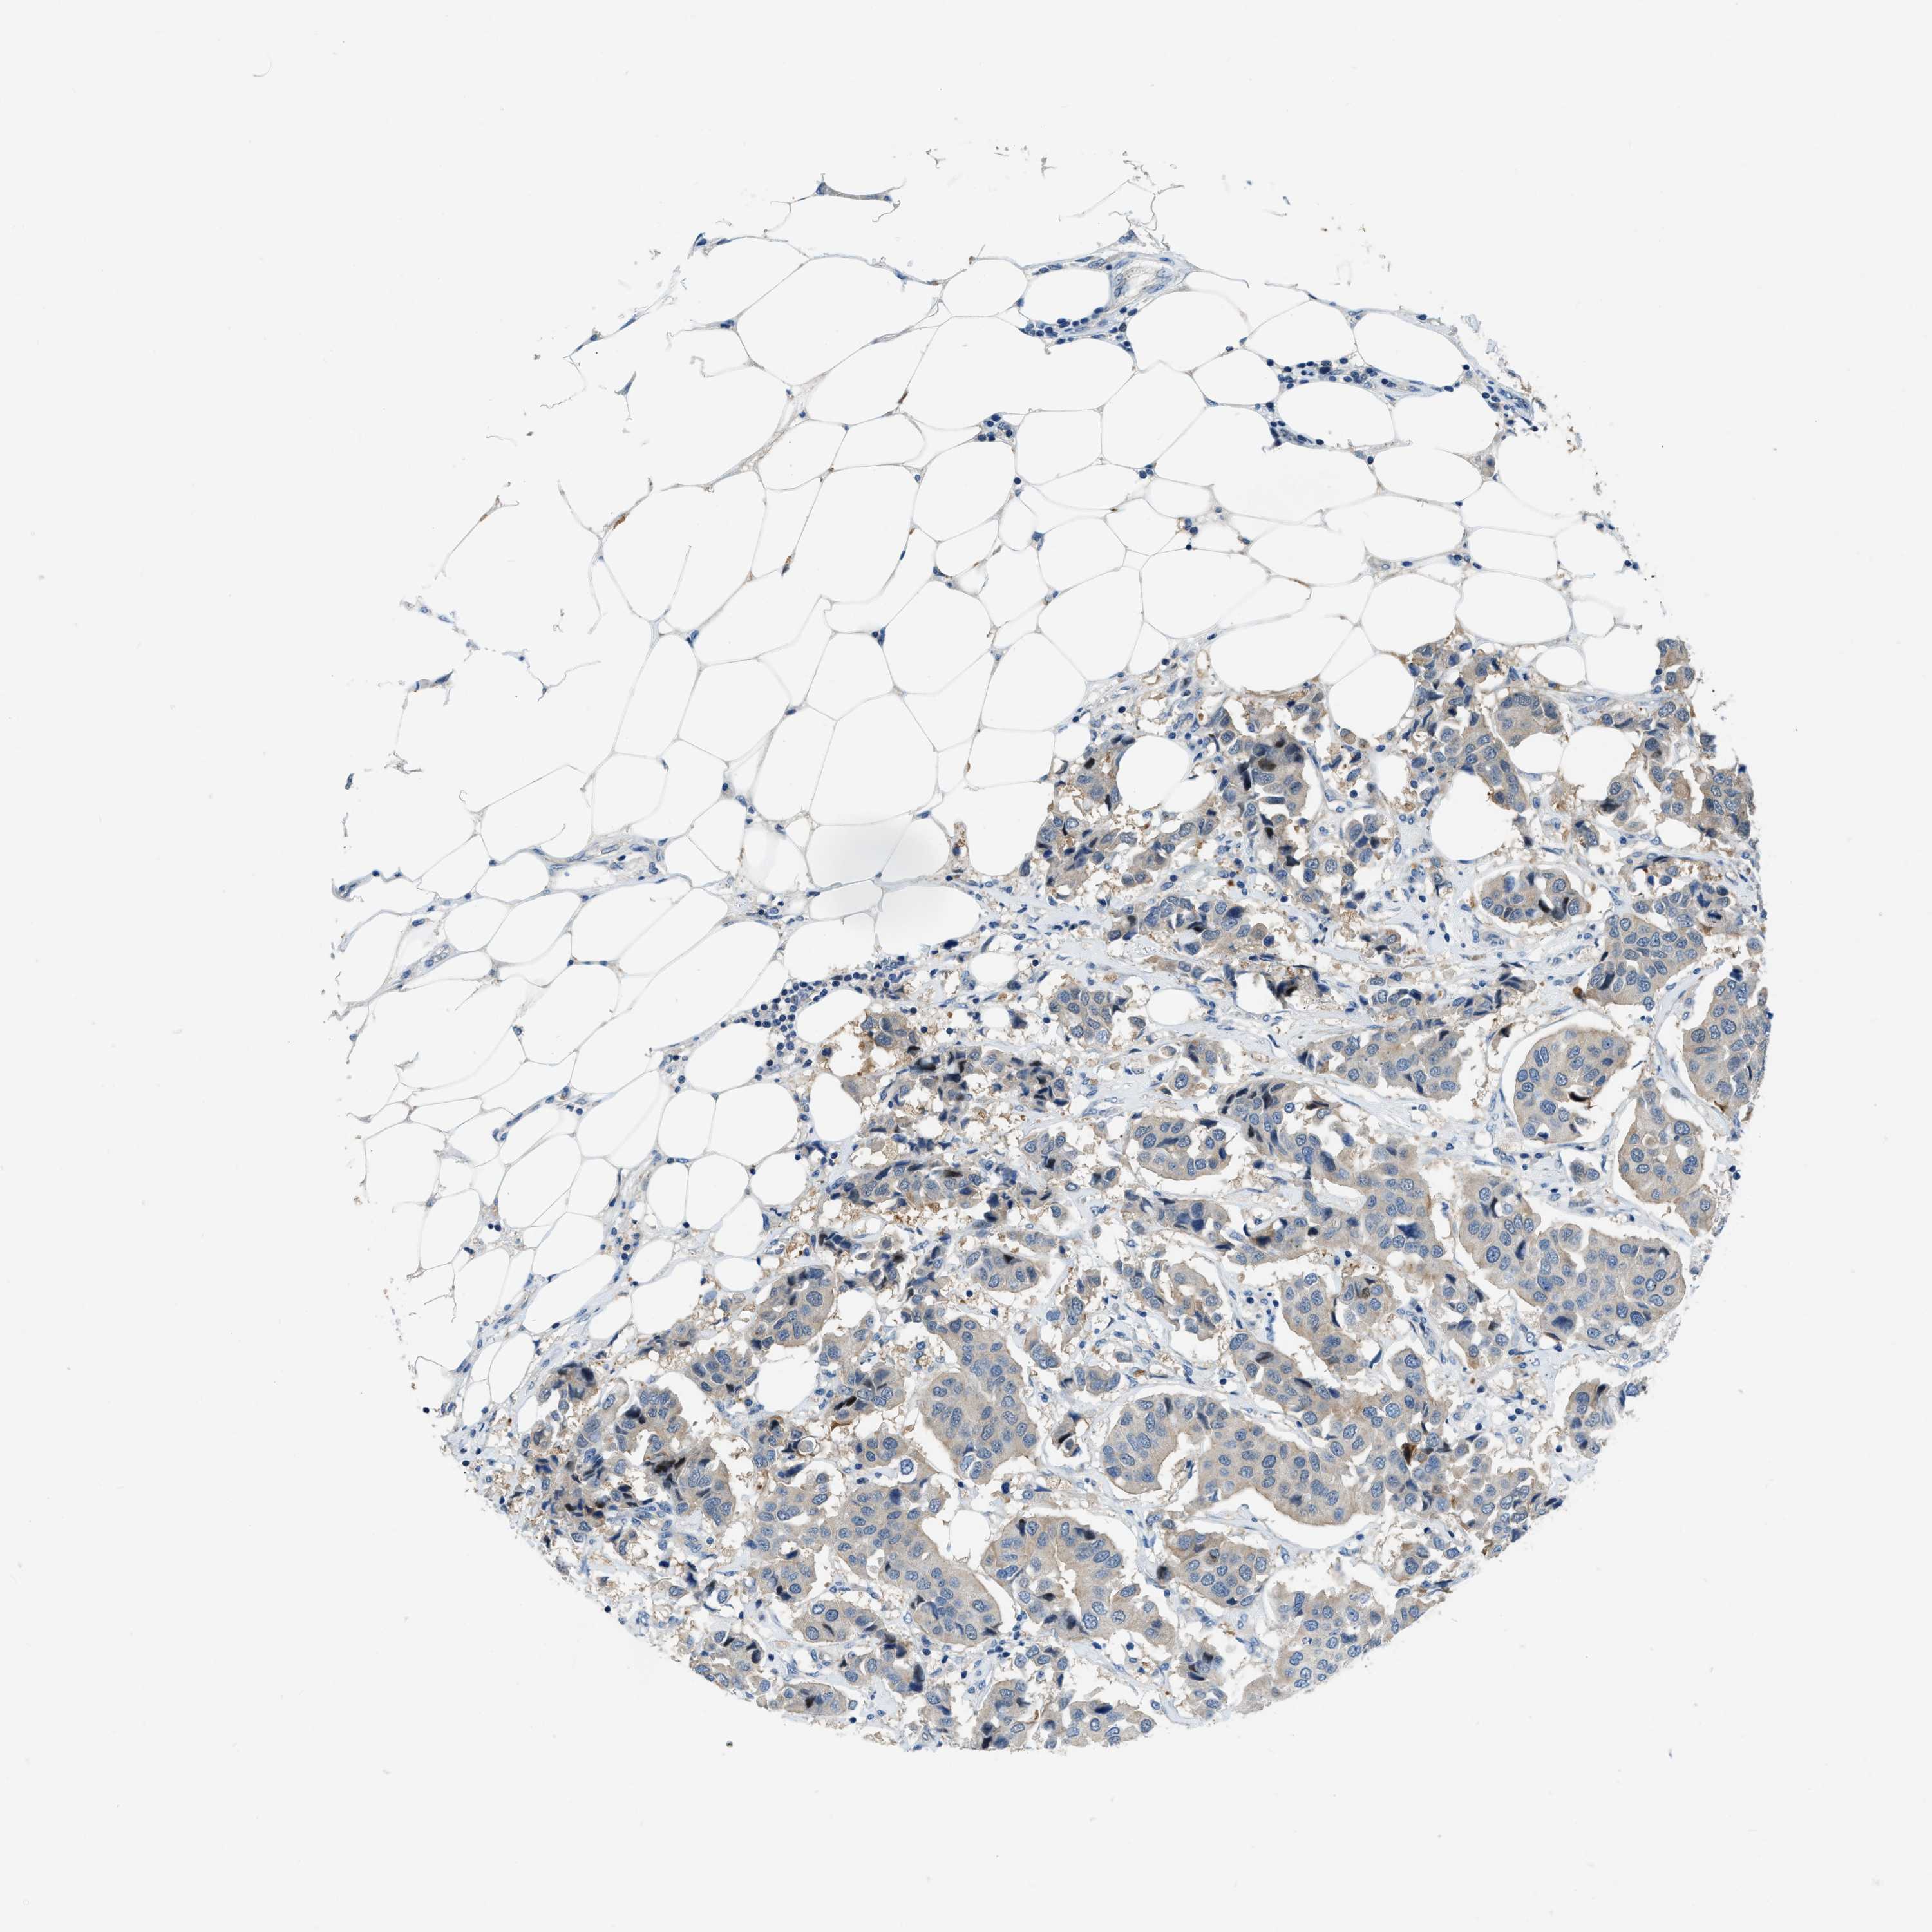

CANCER BREAST CANCER Show tissue menu

BRCA TCGA BRCA VALIDATION PROTEIN EXPRESSION